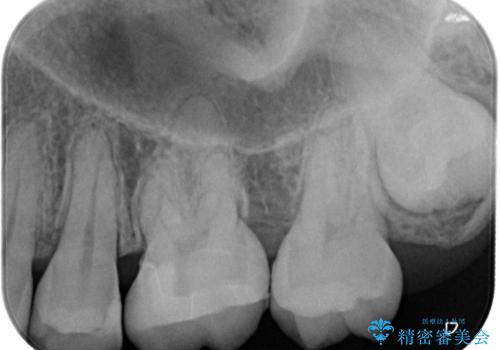

- 矯正終了後にメタルフリーの治療を希望された患者様です。

セラミックインレーにて修復治療を行なっております。

セラミックインレーのセット時にはラバーダムを用い防湿に気をつけて処置をしております。